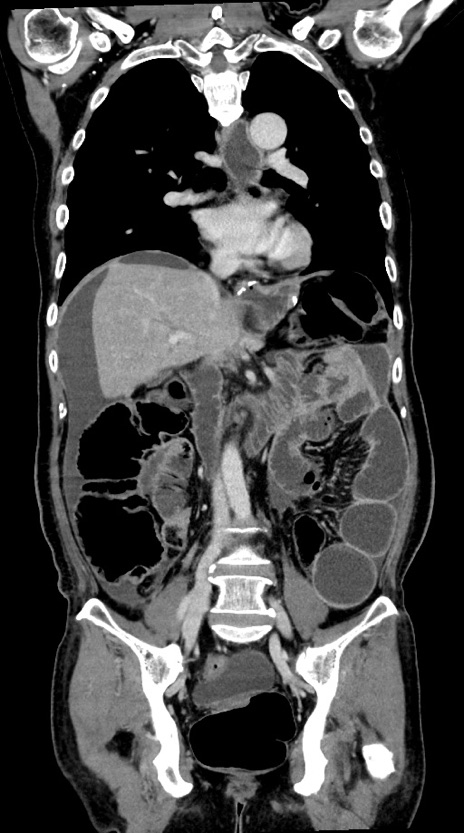

症例28(冠状断像)

【症例】60歳代男性

【主訴】嘔吐

【現病歴】胃癌にて胃全摘後。食思不振が悪化し、夜中に嘔吐することがある。

【既往歴】胃癌、胃全摘、脾摘、胆摘後

【データ】WBC 5900、CRP 10.56